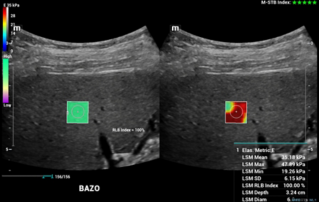

Female pelvic floor anatomy, which developed since the early 20th century, has had a variety of theories, including integral theory, three levels of vaginal support theory, "hammock hypothesis", and three-chamber system. Supporting structures such as pelvic floor muscles, fascia and ligament play an important role in maintaining the normal function of pelvic floor, among which levator ani muscle group is one of the most important supporting structures.